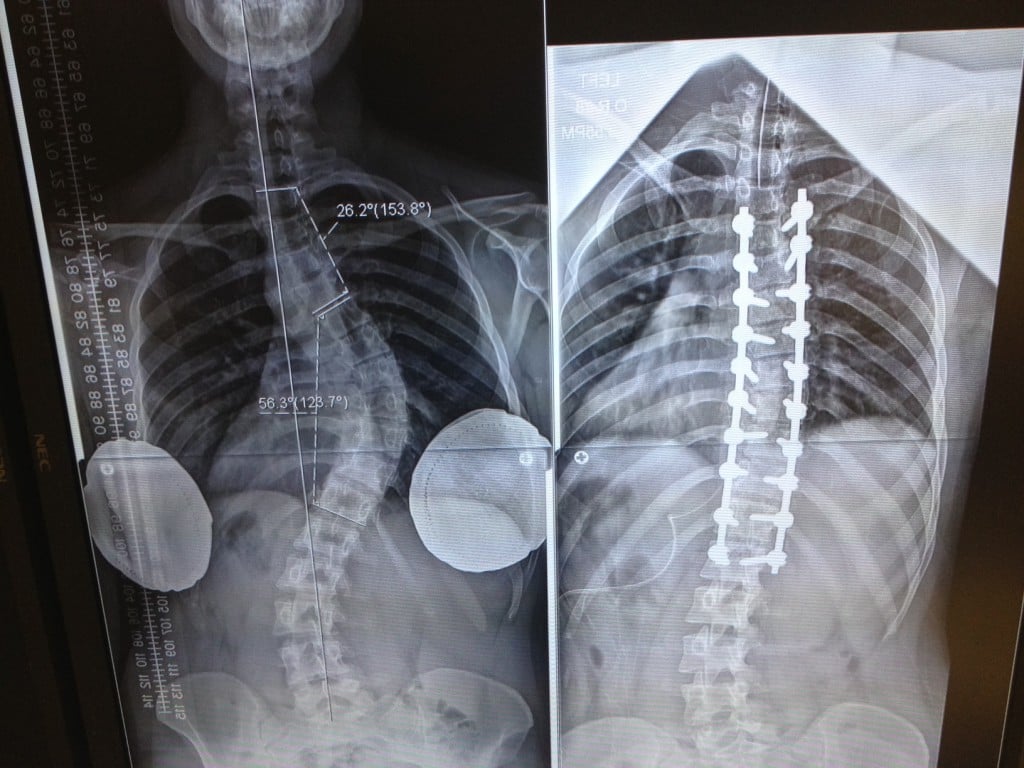

In 2024, Dr. Cammisa treated me with great skill and thoughtfulness, doing the very best he could based on my age and condition. Thanks to his expertise, my life has changed dramatically.